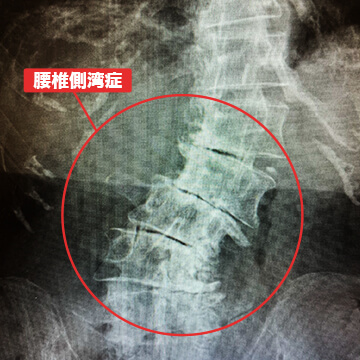

- 腰椎側湾症

腰椎側弯症とは、椎間板や椎間関節の老化によって腰椎が10度以上左右に曲がることを言います。主に腰痛や足の痛みが出現し、側弯が進むと真っ直ぐ立っていても体の左右差が現れます。進行が進むと背骨をボルトで固定する脊椎固定術を選択されることもあります。